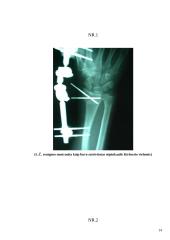

Ligos anamnezė: grudžio 5 dieną tiriamoji ėjo apledėjusiu takeliu į darbą. Paslydo ir griuvo ant dešinio šono, griuvimo metu bandė atsiremti dešine ranka. Kadangi atremtis buvo netaisyklinga bandant atsikelti ji pajuto nepakenčiamą skausmą stipinkaulio srityje. Ligos priežastis buvo vidinis stipinkaulio lūžis. Tiriamoji buvo operuota, operacijos metu stipinkaulis buvo sutvirtintas Kiršnerio vielomis ir išorinės fiksacijos aparatu. Po 4 savaičių tiriamajai išimta ši fiksacija ir buvo pradedama atlikti reabilitacinę rankos mankštą (nors ir fiksacijos metu buvo atliekama lengva pirštų mankšta), atlikta 12 procedūrų.